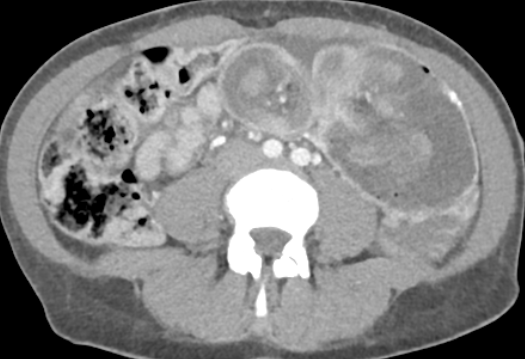

Η αξονική αγγειογραφία αποκάλυψε διάχυτες ασβεστώσεις του αγγειακού τοιχώματος και αθηροσκληρωτικές μεταβολές της κάτω κοιλιακής αορτής και των αμφοτερόπλευρων λαγόνιων αρτηριών, καθώς και έντονη ασβέστωση των μεγάλων και μικρών αρτηριών και των δύο κάτω άκρων. (Ευγενική παραχώρηση Dr. V. Penopoulos).